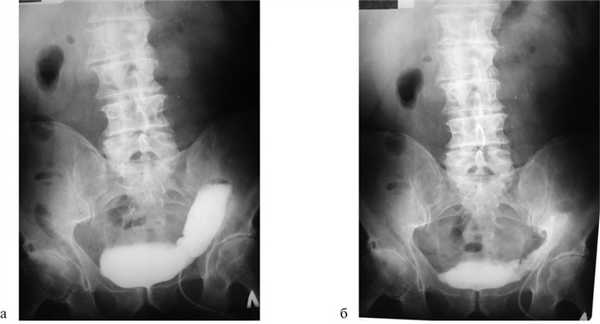

На рис. 2 представлены рентгенограммы больного Н., 63 лет, с наполненным тонкокишечным резервуаром и после его опорожнения через 2 мес после резекции сигмовидной кишки, субтотальной резекции мочевого пузыря с сохранением основания мочевого пузыря с устьями мочеточников и уретрой и тонкокишечной пластикой, свидетельствующие об адекватной функции сформированного тонкокишечного резервуара.

Рис. 2. Рентгенограммы вновь сформированного мочевого пузыря больного Н., 63 лет, через 2 мес после резекции сигмовидной кишки, субтотальной резекции мочевого пузыря с сохранением основания мочевого пузыря с устьями мочеточников и уретрой и тонкокишечной пластикой с наполненным резервуаром (а) и после опорожнения (б).